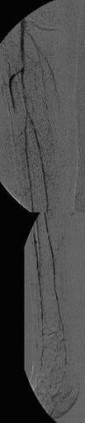

Erfolgreiche Implantation eines transjugulären intrahepatischen portosystemischen Shunts (TIPSS) bei Leberzirrhose und refraktärem Aszites. Implantation eines Stentgrafts

(Bild 4 von 4)